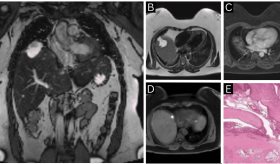

También se emplean estudios por imágenes como ecografía, tomografía computarizada y resonancia magnética. En algunos casos se utiliza la colangiopancreatografía retrógrada endoscópica para observar directamente los conductos y tomar muestras o biopsias.